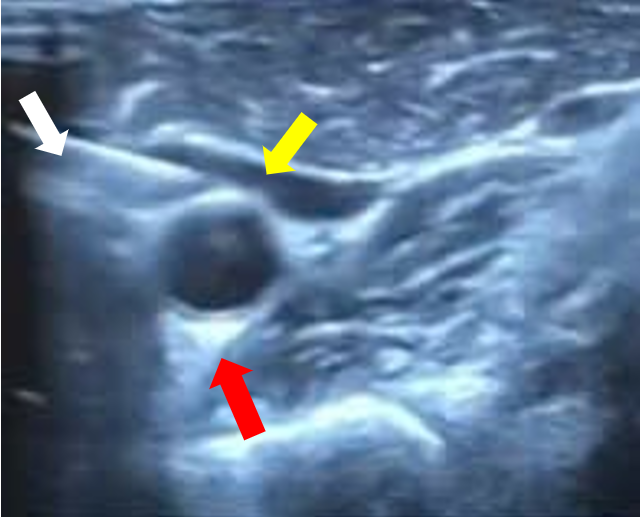

Chọc hút hạch nghi ngờ sát động mạch cảnh dưới hướng dẫn siêu âm (mũi tên trắng: kim sinh thiết, mũi tên vàng: hạch nghi ngờ, mũi tên đỏ: Động mạch cảnh)

Chọc hút hạch nghi ngờ sát động mạch cảnh dưới hướng dẫn siêu âm

(mũi tên trắng: kim sinh thiết, mũi tên vàng: hạch nghi ngờ, mũi tên đỏ: Động mạch cảnh)